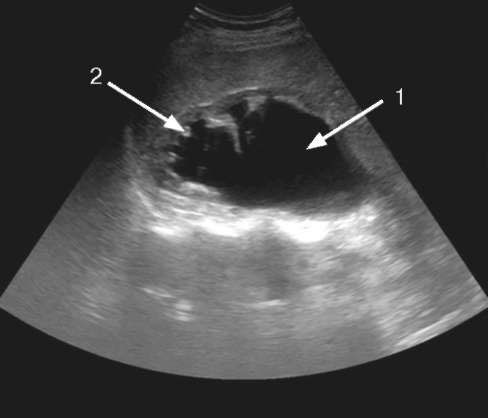

Схематичное изображение процесса гидронефроза.

Одним из самых частых осложнений пиелоэктазии является гидронефроз.

При развитии гидронефроза патология проходит три этапа – вначале лоханка расширяется незаметно, почти без симптомов, затем увеличиваются в размерах другие части почки, что в целом нарушает функционирование органа, и, наконец, происходит истончение тканей и возможный склероз почки. Поэтому оставлять ситуацию без контроля недопустимо.